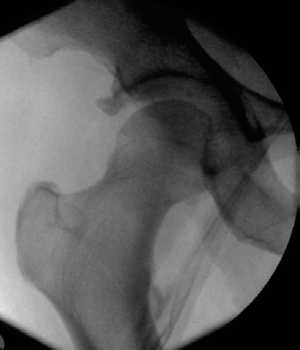

Lower limb Trauma Structured oral examination question 8 A 72-year-old woman, fully independent with good hea…